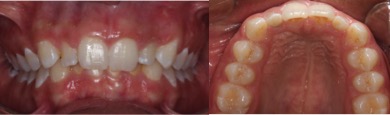

Dens in dente is a dental development malformation that involves more commonly the upper lateral incisors. Infection of the canal of these teeth can cause the formation of chronic periapical lesions. The present study aimed to describe an integrated approach between the endodontic therapy and surgical intervention in an upper lateral incisor with dens in dente type II. A female patient, 14 years old, looked for dental care complaining of left palatal and paranasal bulging. Clinical, radiological and histopathological findings suggested periradicular cyst. First, marsupialization was performed to reduce the size of the lesion and to favor its enucleation, with less risk of injuring the tooth and vital structures. After diagnosis of pulp necrosis and in attempt to reduce the infection via canal, we used the reciprocating instrumentation associated with irrigation with sodium hypochlorite, intracanal medication based on calcium hydroxide and filled with a thermoplastic filling. After a year of marsupialization, fistulectomy and complete enucleation of the lesion were performed. Proservation was performed 1, 3, 6 and 12 months following marsupialization. Six months after enucleation, we observed the periradicular repair and remission of symptoms. The extensive apical lesion associated with dens in dente type II can be treated with a combination of surgical and endodontic therapy.